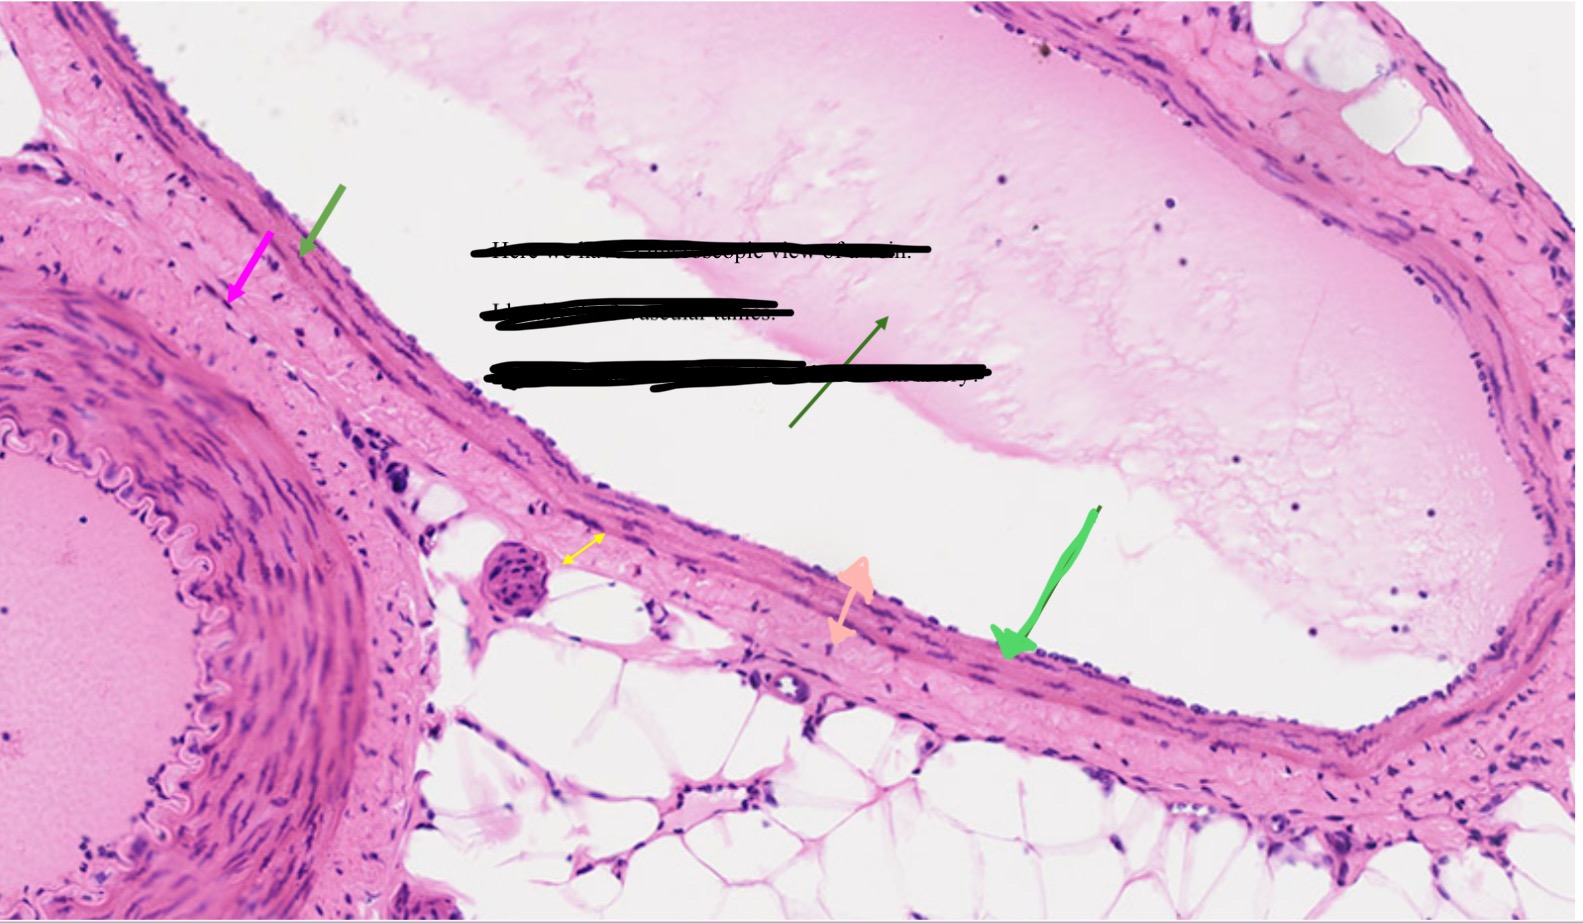

Venous valves

Name the pink arrow

Prevent backflow of blood

Function of venous valves

Artery

Artery or vein?

Vein

Artery or vein?

Tunica interna

Name the green

Tunica media

Name the pink

Tunica externa

Name the yellow